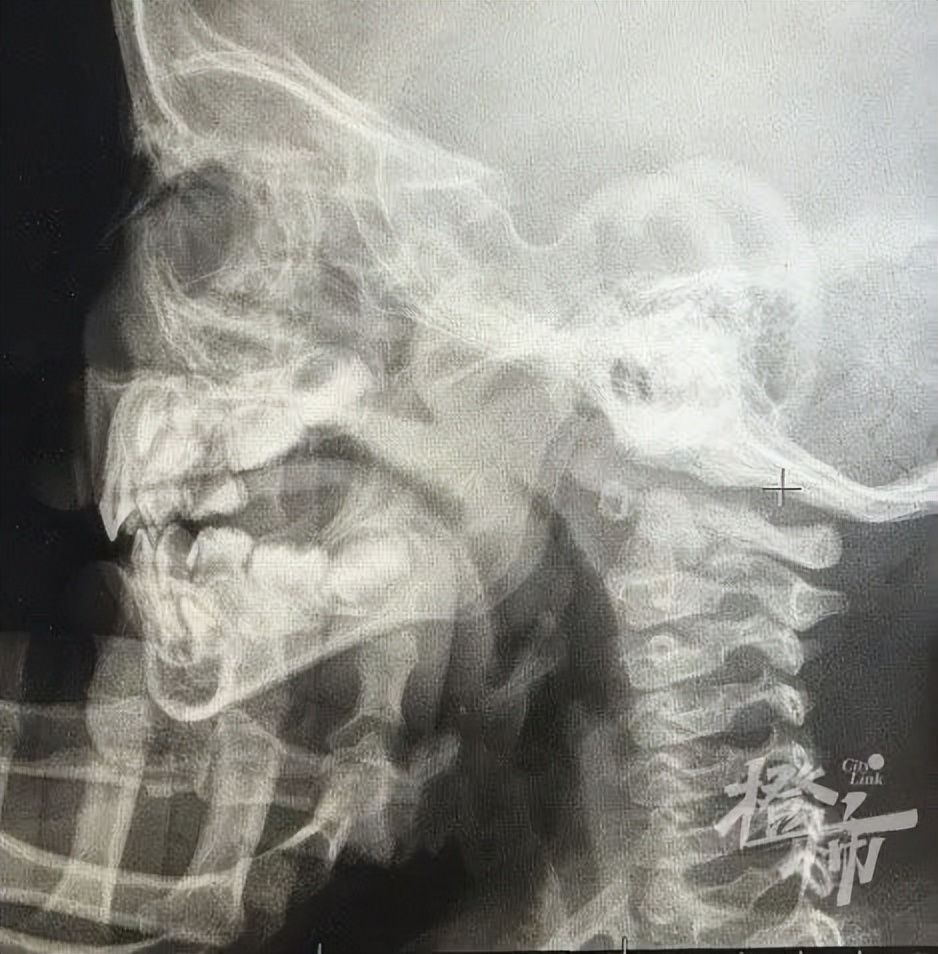

“赶紧不要贴了!”听到这里,刘湘医生赶紧阻止,“根据孩子的病情和检查结果来看,不适合用闭口贴。”在电脑上,刘湘打开了笑笑的鼻腔部位的x光片, 只见笑笑的鼻腔鼻窦已经呈现大片“絮状”,鼻咽部腺样体显著肥大,这意味着笑笑的鼻腔以及鼻咽部堵塞非常严重。“堵塞这么严重的情况下,还给孩子贴嘴巴,气都喘不过来了。”